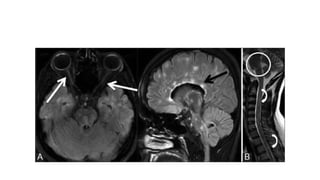

A-Neurological lesion

(tumor-MS)

Compressive lesion,tumor ,pitutary adenoma

MS lesion